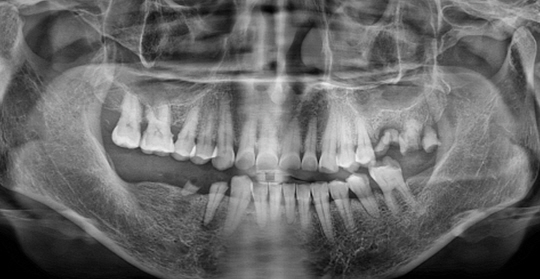

(66세 여 환자)

(38세 남 환자)

(61세 남 환자)

(50세 남 환자)

(63세 남 환자)

(59세 여 환자)

(67세 남 환자)

(45세 남 환자)